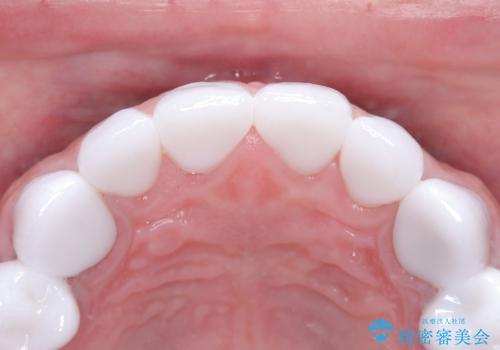

前歯のクラウンをやり変え、歯肉のラインも美しく

- 治療計画

治療では、まず古いクラウンを慎重に取り外し、歯肉の状態を整えました。その後、精密な型取りから患者様一人ひとりに合わせたオーダーメイドのオールセラミッククラウンを作製。金属を一切使用しないため、歯肉の変色を防ぎ、天然歯のような透明感と美しさを再現します。新しいクラウンは、歯肉のラインに合わせてぴったりと適合するよう調整し、見た目の違和感を解消。長年の悩みが解決し、自然で美しい口元と笑顔を取り戻していただけました。